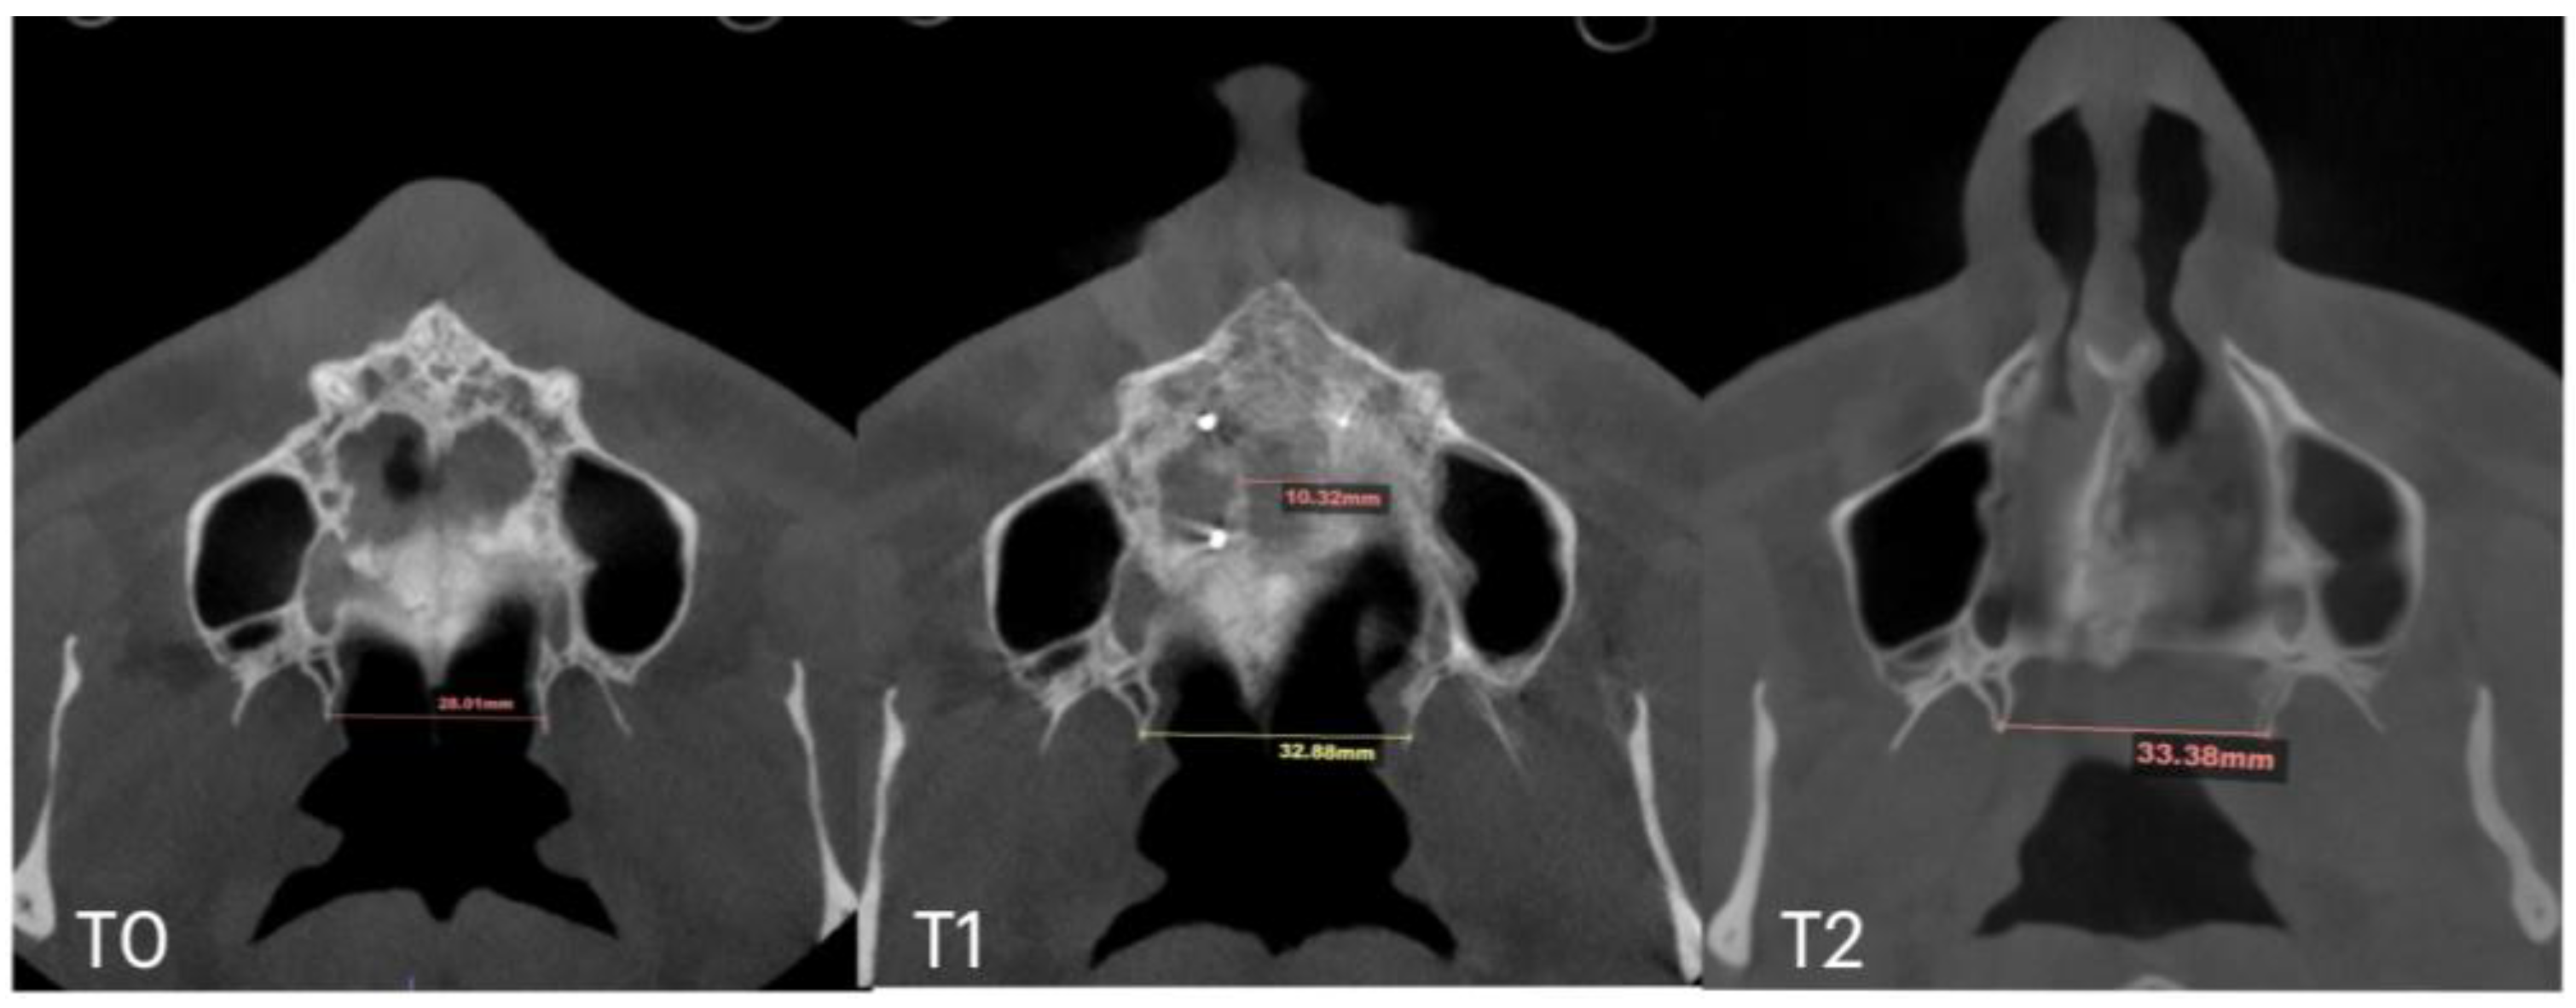

| Case A | 30.84 | 38.15 | 38.37 | 59.22 | 66.37 | 67.11 | 32.8 | 39.33 | 39.48 | 28.01 | 32.88 | 33.38 | 10.5 |